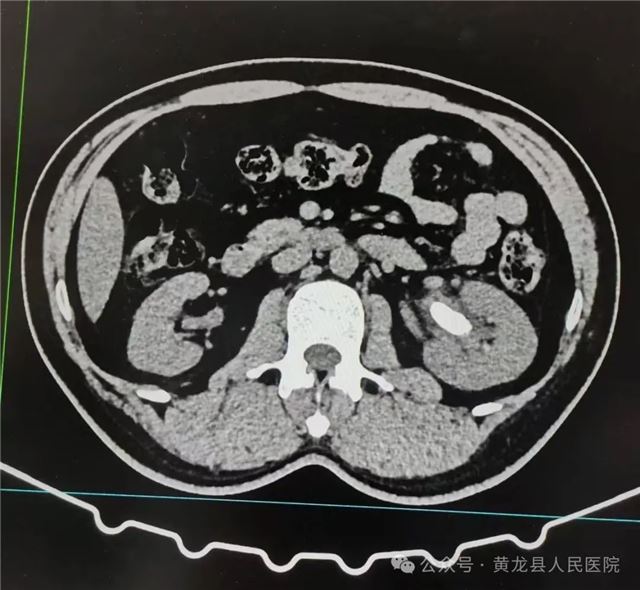

术前CT影像